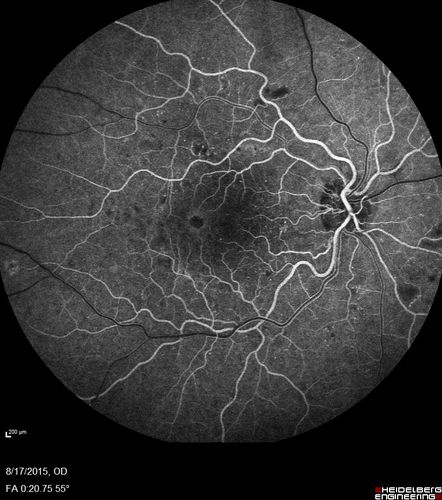

West Nile Virus Multifocal Choroiditis and diabetic retinopathy

Multifocal and clustered focal lesions are from west nile virus. The retinopathy is probably diabetic but could also be related to west nile virus